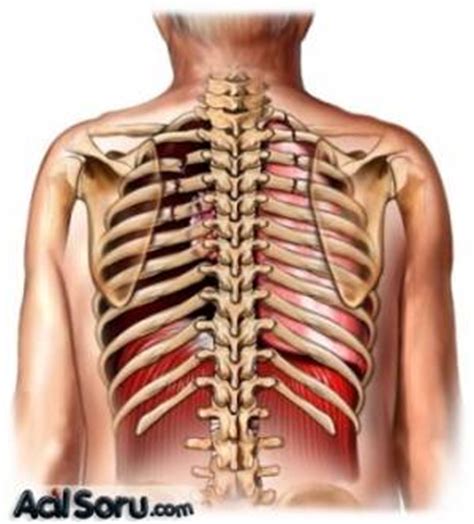

Sağ kaburga kemiğinin altında bulunan organ karaciğerdir. Karaciğer, vücudumuzdaki en büyük iç organlardan biridir ve birçok önemli fonksiyona sahiptir. Sindirim sisteminde önemli bir rol oynar, vücudu toksinlerden arındırır, enerji depolar ve birçok hayati süreci düzenler.

Karaciğerin sağ kaburga kemiğinin altında bulunması, vücudumuzdaki anatomik yapının bir parçasıdır. Sağ kaburga kemiği, karın boşluğundaki organları koruyan bir yapıdır ve karaciğer de bu koruma altındadır. Karaciğer, sağ üst karın bölgesinde, mide ile bağırsaklar arasında bulunur ve diyaframın hemen altında yer alır.

Karaciğerin sağ kaburga kemiğinin altında bulunması, bu organın korunmasını sağlar ve dış etkenlere karşı daha az savunmasız olmasını sağlar. Karaciğerin sağ kaburga kemiğinin altında bulunması, aynı zamanda bu organın işlevlerini daha etkin bir şekilde yerine getirmesine yardımcı olur.